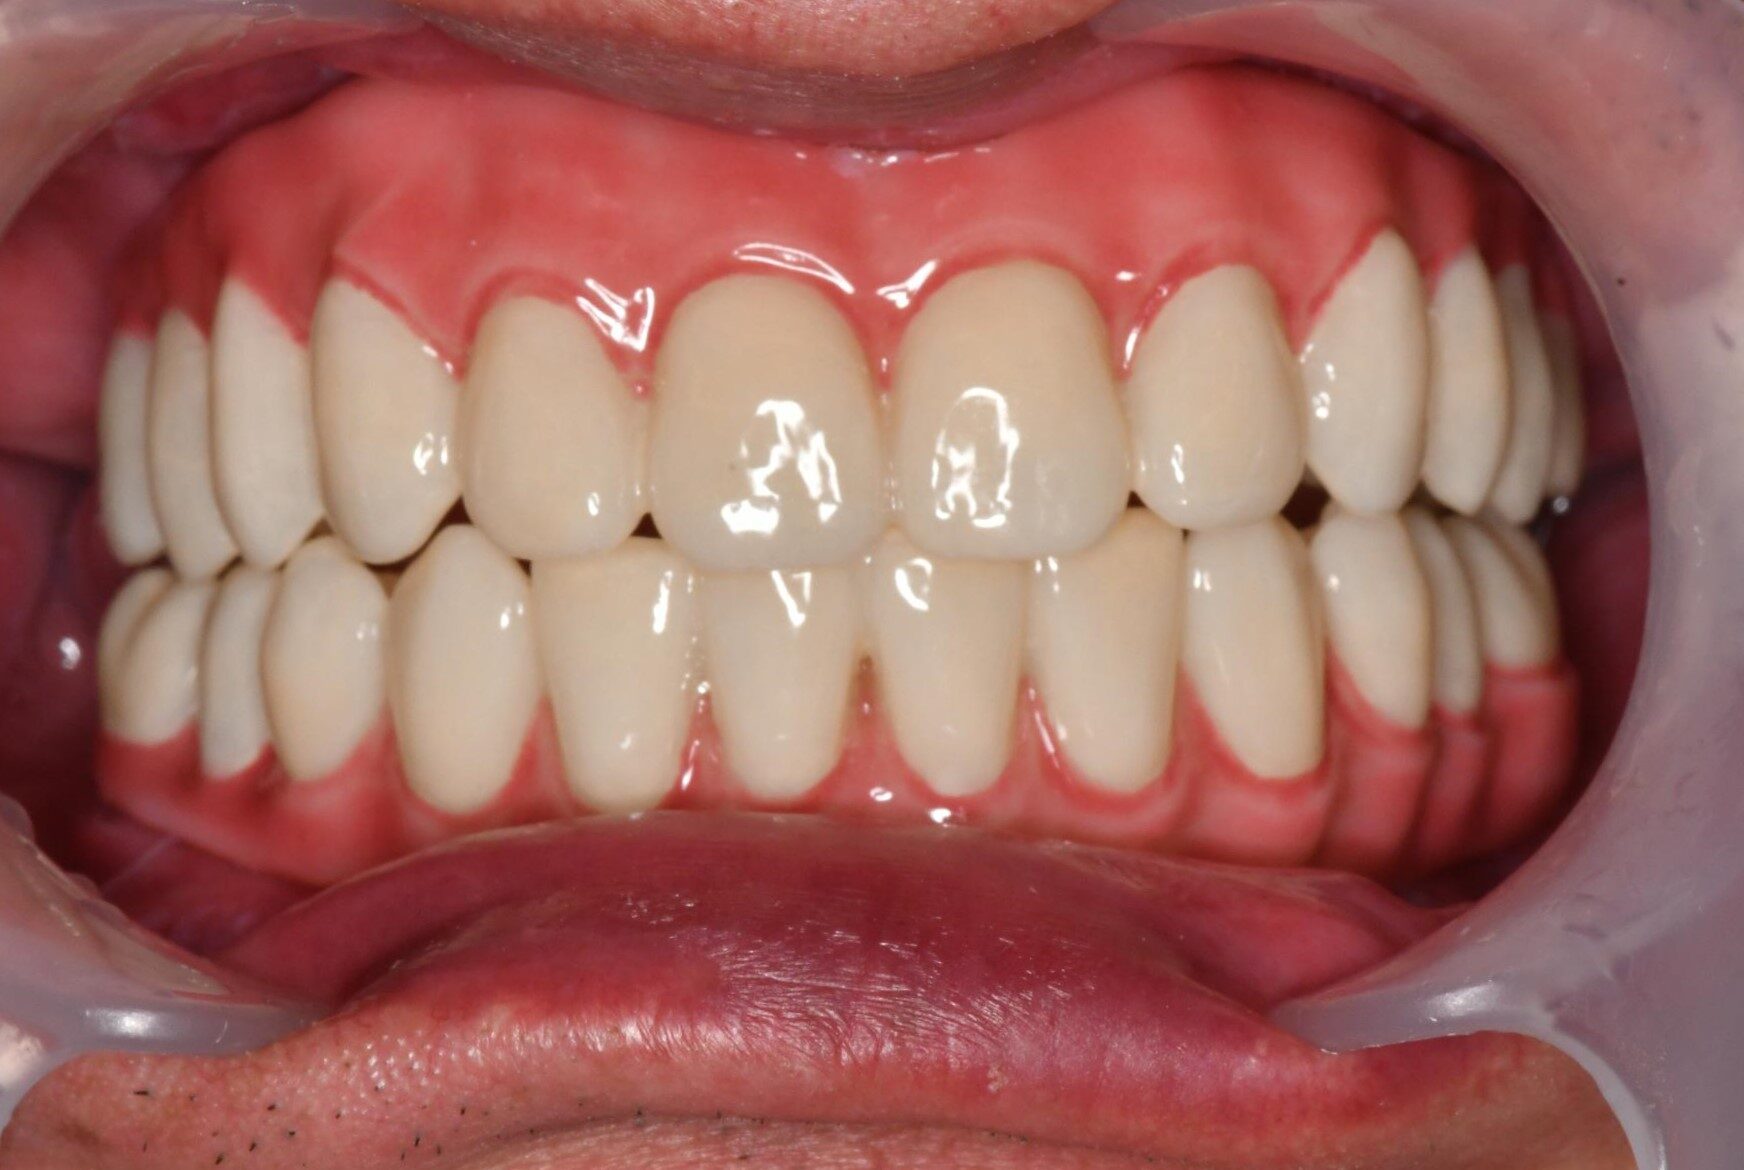

当院ではしっかり噛めるという機能性はもちろんのこと、審美性(見た目の美しさ)も徹底的にこだわり設計します。

装着される歯は全て3Dデータ化され、最新のCADソフトウェアにて製作します。

また、独自特許のフェイシャルスキャンボディにより患者様ごとの顔に対して、より整合性の高い本歯の提供が可能となります。(特許6437699号)

上下All-on-4

上顎:オールオン4ザイゴマ4本

下顎:オールオン4

Before

After